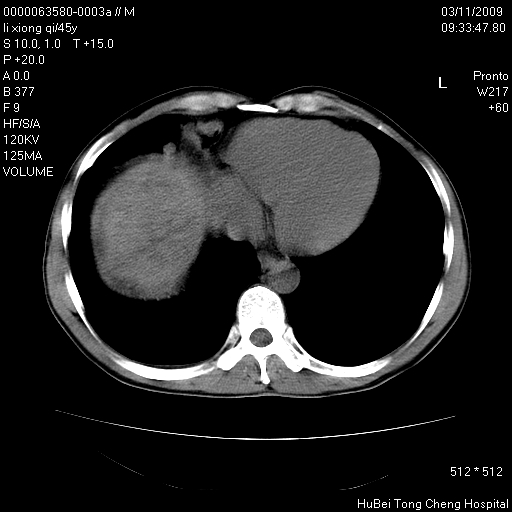

患者 男,45岁。胸痛,咳嗽伴痰中带血1月余。

临床诊断:肺结核?

胸部ct轴位平扫(层厚10mm,螺距1.5,重建间隔10mm),图像如下:

考虑肝癌肺转移